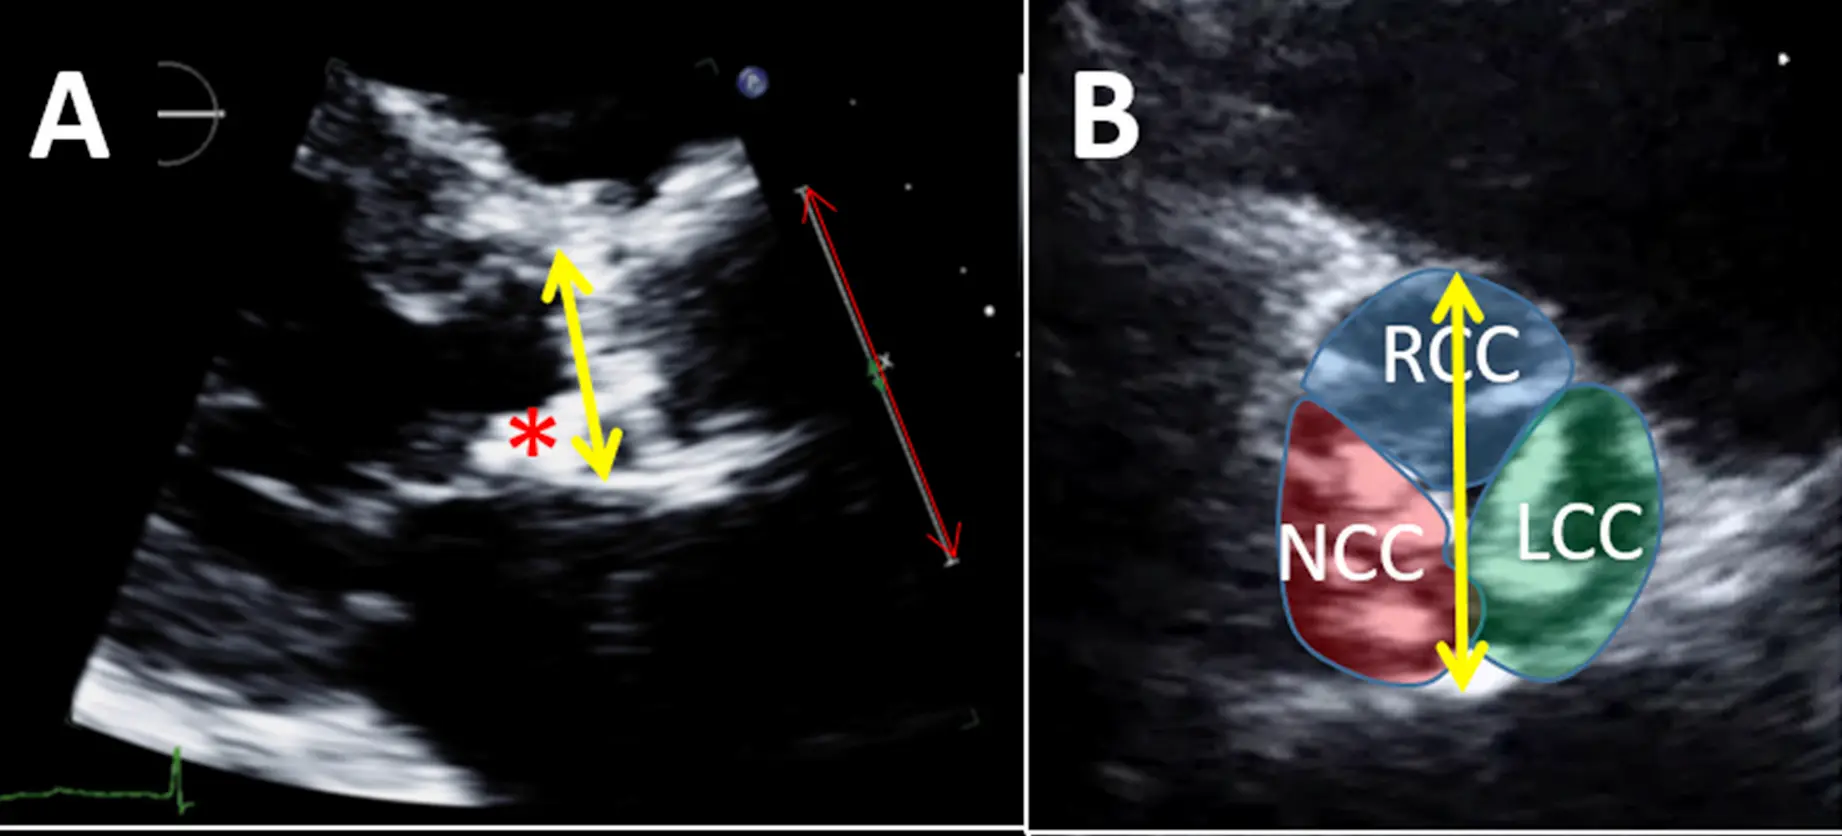

- Measuring LVOTd at the aortic annulus and not 0.5 to 1 cm below

- In the presence of LVOT ectopic calcification: using the plane that bisects the largest diameter but excludes the calcification from the LVOTd measurement (Figure 1A).